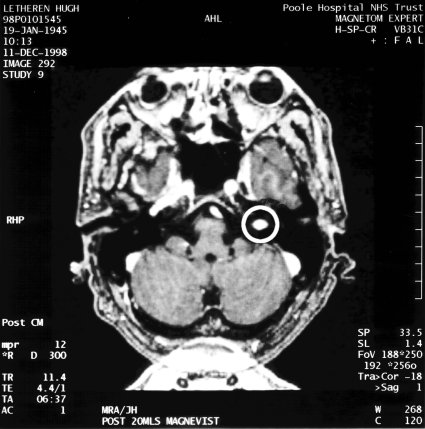

MRI Scan 1998

This is a horizontal slice through the head at eye level, viewed from underneath. The front of the head is at the top and the tumour is highlighted, 3cm from the left ear, which appears on the right of the scan. The scale marks are at 1cm intervals, from which it can be seen that the tumour is about 1cm in diameter - fortunately it was diagnosed when it was really quite small.